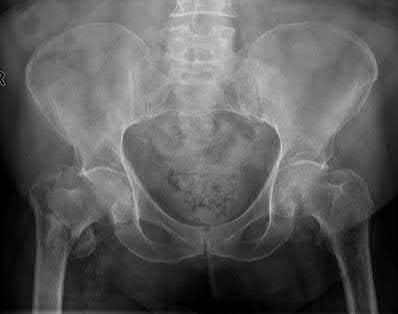

A 35-year-old man presents to the ED as the restrained driver of a high speed motor vehicle collision complaining of hip, chest, and abdominal pain. He becomes diaphoretic, tachycardic, and hypotensive in the trauma bay and is noted to have diminished lower extremity pulses. He is found on ATLS workup to have mediastinal widening.

Which of the following injuries is most associated with thoracic aortic injury?

Thoracic aortic rupture is associated with posterior hip dislocation in deceleration trauma mechanism of injuries.

Posterior hip dislocations are infrequently associated with local vascular injuries. With bilateral perfusion deficits, more proximal large vessel trauma should be considered, and in this situation, thoracic surgery should be involved emergently. Screening chest x-ray in the trauma bay should be reviewed for widened mediastinum, suggestive of aortic injury, as shown in illustration A. Given the high energy mechanism associated with these injuries, a full ATLS trauma survey must be done for every patient.

Marymont et al. studies the association between posterior hip dislocation and thoracic aortic injury. They performed a retrospective chart review of 89 posterior hip dislocations and found 8% had an aortic injury. Although not statistically significant, they note the importance of evaluation for aortic injury in patients with posterior hip dislocations given its emergent life-threatening nature.

In addition to associated chest injuries, Schmidt et al. highlight the importance of evaluating the ipsilateral knee after high-energy traumatic hip dislocation. In a prospective study, they identified a 93% rate of ipsilateral knee injury on MRI including effusion (37%), bone bruising (33%), and meniscal tear (30%) as the most common. They recommend a thorough exam but also expanded use of knee MRI after hip dislocation.

Illustration A shows an example of chest x-ray with a widened mediastinum, suggestive of thoracic aortic injury.

Answer choices A,B,D,E show other injury patterns: Answer A - Right femoral neck fracture

Answer B - Right intertrochanteric hip fracture Answer D - Right subtrochanteric hip fracture

Answer E - Right superior and inferior pubic rami fractures